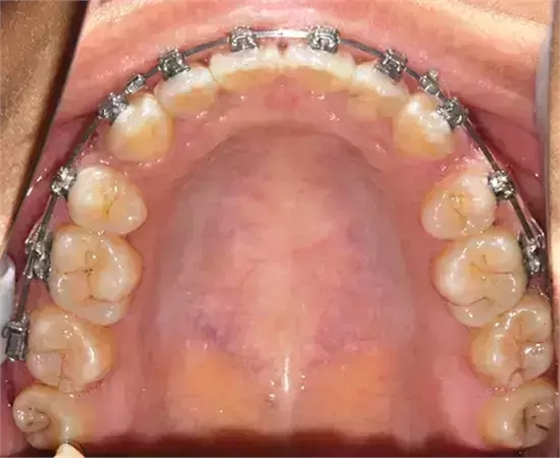

上下牙列擁擠,磨牙尖牙Ⅱ 類關(guān)系,3 度的深覆牙合,上頜中切牙伸長內(nèi)傾拔除上頜雙側(cè)的第一前磨牙,先粘上頜高轉(zhuǎn)矩的自鎖托槽排齊牙列,唇向開展上頜切牙,有一定的覆蓋,粘下頜標準轉(zhuǎn)矩托槽,上頜 1, 2 之間植入種植支抗壓入,同時后牙 5, 6 之間植入種植支抗內(nèi)收前牙,打開咬合關(guān)閉間隙。治療關(guān)鍵:前牙轉(zhuǎn)矩的控制第 1 個月 上頜粘上 Damon Q 高轉(zhuǎn)矩托槽,上 .014 熱激活 NiTi 絲。第 3 個月 上換 .014 x .025 熱激活 NiTi 絲。第 5 個月 上頜基本排齊,覆蓋增大,上換 .017 x .025 NiTi絲,下頜粘托槽,下 .014 熱激活 NiTi 絲。第 7 個月 上 .017 x .025 NiTi 絲加搖椅,下?lián)Q .014 x .025 熱激活 NiTi 絲第 9 個月 上頜換 .019 x .025 NiTi 絲加搖椅,下頜換 .017 x .025 NiTi 絲第 11 個月 下頜換 .019 x .025 加搖椅,上頜 1, 2 之間, 5, 6 之間植入種植釘,下頜出現(xiàn)散隙。第 13 個月 上頜換 .019 x .025ss 加搖椅,前牙種植釘用 Power Chain 壓低前牙(每側(cè) 100g),后牙種植釘關(guān)閉間隙(每側(cè) 150g),下?lián)Q .019 x .025ss,Power Chain 關(guān)閉間隙。第 19 個月 上頜前牙基本壓低到位去除前牙種植釘,繼續(xù)用關(guān)閉間隙,下頜散隙關(guān)閉。